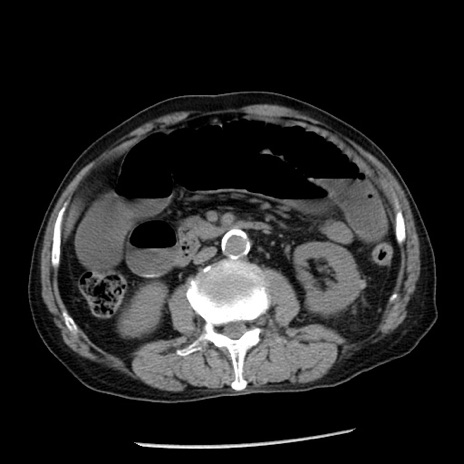

冠状断像

【症例】80歳代男性

【主訴】嘔吐

【現病歴】昨晩2回嘔吐あり、今朝になっても嘔吐あり。来院。

【既往歴】胃潰瘍

【身体所見】意識清明、BT 37.6℃、BP 166/95mmHg、HR 100bpm、SpO2 97%、腹部:平坦・軟、腸蠕動音聴取良好、圧痛なし。

【データ】WBC 21900、CRP 1.46